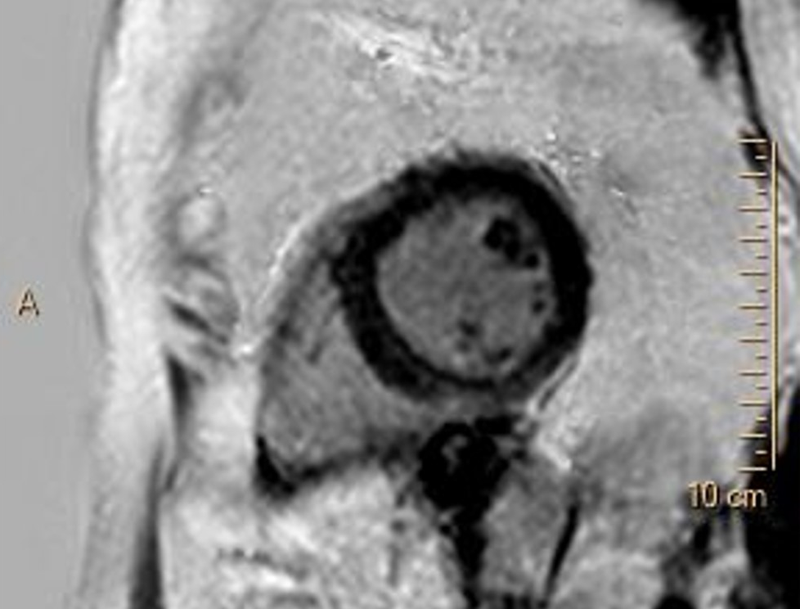

Vyšetření MRI srdce je bez známek edému myokardu a pozdního gadoliniového sycení (LGE) – nezjistilo tedy přítomnost zánětu, nekrózy, nahrazující fibrózy či infiltrace myokardu. Levá komora hodnocena při MRI jako mírně dilatovaná s EF 39 % (obrázek 2, video 4). Laboratorní vyšetření CK, LDH a železa, provedené k vyloučení dalších možných etiologií DKMP, bylo bez významné patologie, hodnota NT-pro BNP poklesla na 1 120 ng/ml.

Obr. 2. MRI srdce. 2A – nepřítomnost edému myokardu v T2 STIR TSE sekvenci v krátké ose, 2B – IR TFE sekvence v krátké ose – bez detekce pozdního sycení myokardu (LGE)

Video 4. MRI srdce, B-TFE sekvence v dlouhé ose – mírná dilatace a difúzní hypokineze stěn LK s EF 39 %

Na základě provedených vyšetření se domníváme, že etiologií srdečního selhání je u nemocné nejspíše dilatační kardiomyopatie na podkladě kardiotoxického postižení myokardu protinádorovou léčbou antracykliny – pozdní kardiotoxicita. Vzhledem ke zlepšující se systolické funkci LK s EF 39 % dle MRI jsme ustoupily od přístrojové léčby – implantace ICD.